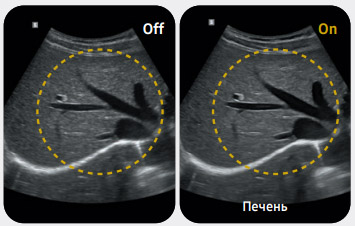

Расчет печеночно-почечного индекса с автоматической установкой областей интереса

HRI (Печеночно-почечный индекс) — это количественный показатель стеатоза печени, получаемый путем сравнения эхогенности паренхимы печени и коркового вещества почки. Функция EzHRI™ автоматически размещает 2 области интереса на паренхиме печени и корковом веществе почки с последующим расчетом показателя HRI.